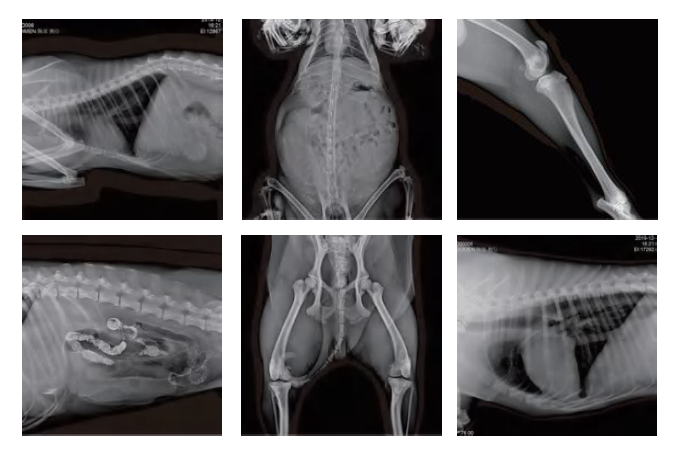

CFV-DR320V 32KW Digital X Ray Machine

.Software:Professional veterinary software